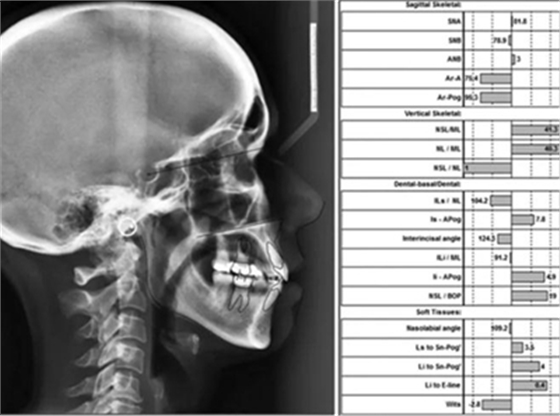

頭影測量分析,SNA角84°,ANB角6°,高角型,詳見下表。

患者側(cè)貌改善,下唇唇肌緊張消失,上下唇可自然閉合。磨牙及尖牙關(guān)系糾正至I類,覆合覆蓋正常。上下頜弓型糾正至卵圓形,牙弓寬度增加。頭影測量分析示SNA角81.8°,ANB角3°。頭影測量重疊圖示下頜骨向后旋轉(zhuǎn),垂直面高度略有增加。